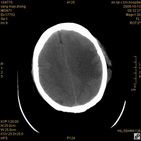

术后46小时复查CT

术后46小时复查1 术后46小时复查2 术后46小时复查3 术后46小时复查4